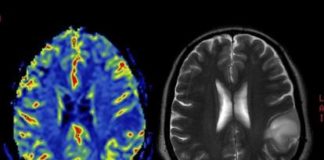

Zapanjujuće otkriće: Evo što vašem mozgu radi smog! Oni koji su živjeli u zagađenijim područjima kroz 10 godina praćenja imali su smanjenje volumena mozga...

"Alzheimer mijenja mozak puno prije dijagnoze." Znanstvenici na tragu krvnog testa. Britanski znanstvenici otkrili su u krvi deset proteina koji mogu predvidjeti pojavu Alzheimerove...